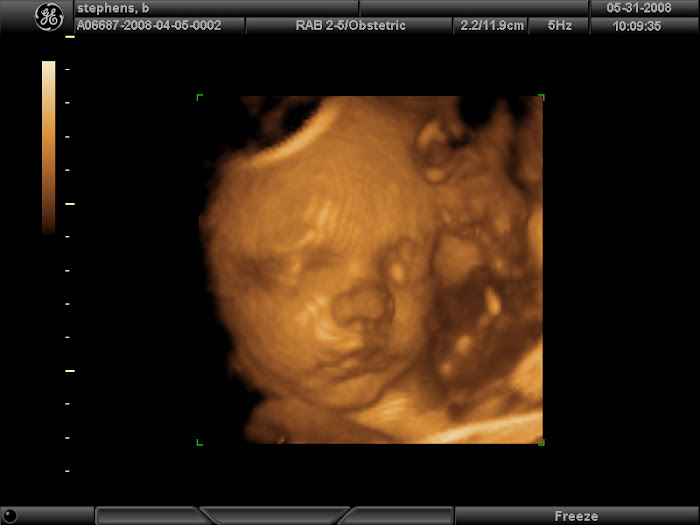

So... as most of you already know, Beau, Georgia and Savannah and I have welcomed a new addition to our family. Born on July 29th, 2008 - all 8 pounds 11 ounces of him... Beau Dale Stephens came into this world.

During my 7th month of pregnancy, an ultrasound found a small 3cm cyst inside Little Beau's abdomen. We go tomorrow, Friday August 22nd to have a CT scan done to find out more on this cyst. We have been doing a lot of praying and hopefully it will turn out to be nothing at all.